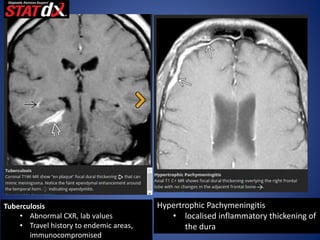

Tuberculosis

• Abnormal CXR, lab values

• Travel history to endemic areas,

immunocompromised

Hypertrophic Pachymeningitis

• localised inflammatory thickening of

the dura

Tuberculosis • Abnormal CXR,lab values • Travel history to endemic areas, immunocompromised Hypertrophic Pachymeningitis • localised inflammatory thickening of the dura